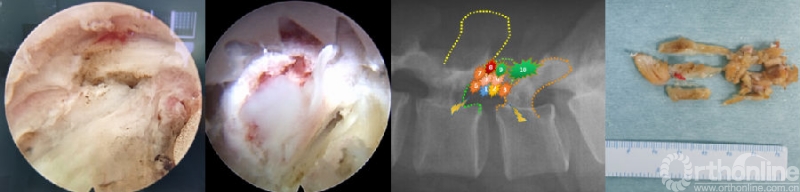

(8) 镜下结构识别和椎管减压

清晰显露关节突关节非常重要,需明确显露关节间隙,遇到有严重骨性关节炎的病例,需术前仔细阅片,了解增生情况,必要时环锯或大号髓核钳预处理表面骨质,直至显露清晰的关节面。上关节突尖部连同部分下关节突作为第一次环锯的位置,较为重要,能够直接显露腹侧黄韧带结构,依次为中心向头尾及背侧充分减压。

头侧注意出口根伴行血管,尾侧注意避免头倾过大而直接锯入椎弓根上缘,这两种情况均会导致大量出血,因此我们大多按照图中所示,由头侧向尾侧,由外侧向内侧,逐步扩大椎间孔区并向椎管减压;黄韧带的头尾端止点及外侧止点的显露尤其重要,内侧显露根据减压来决定,必要时可减压到对侧外侧止点,也就是借助于T的入路完成全椎管的减压-ULBD。

对于行走根与出口根,根据手术需要来决定是否同时显露,一般来讲,L5S1节段需要显露出口根。一旦能够显露黄韧带止点,则术中可以整块切除黄韧带,大大提高手术效率。在此过程中,熟练掌握可视化环锯技术是提高手术效率和安全性的前提,为了防止出现打滑,往往需要先缓慢逆时针进入外层骨质,然后再往复旋转快速进入,最后顺时针至内层骨质,借助不断地摩擦力增加,可将内层骨质掰断,而不是将环锯锯齿穿破骨质及黄韧带。

(9)椎间盘准备与终板处理

神经减压充分后,术野电凝止血,充分显露椎间隙后外侧,U套管向内适当牵开硬膜及神经根,T套管向外牵开软组织,用蓝钳或弧形骨凿锐性剪开纤维环至上下软骨终板,大小髓核钳预处理椎间盘组织,显露椎体上下边缘;对于椎间盘的处理可以采用多种工具,如U-T型双套管组合对软骨终板的旋切,可以在直视下整块切除软骨终板至终板下骨,结合方向的摆动,达到扇形的面积以及前方至前纵韧带,保证植骨面的充足。

目前效率更高的内镜融合处理套装已经成熟使用,如镜内铰刀、镜外铰刀、镜外方凿、镜外偏心刮刀等,均可全程直视完成椎间隙处理;如果椎间隙严重狭窄,还可以在U套管内采用开放手术的6-8号铰刀、椎间隙处理工具等盲视下处理,最后通过内镜来检查处理的效果。操作轻柔,避免损伤终板,是减少椎间融合器下沉、移位的重要环节。另外,行走根及硬膜腹侧的纤维环结构需要部分切除,以便于放置保护行走根的“舌形”工作套管。